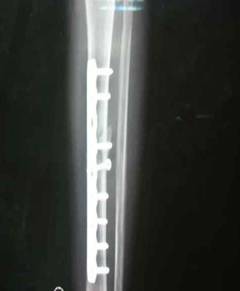

患者小林,一年前因胫腓骨骨折,小腿置入了固定钢板。今日回院复查,患者恢复良好。管床崔医生,已为其办理了住院,择期手术取内固定钢板。

胫腓骨内固定钢板